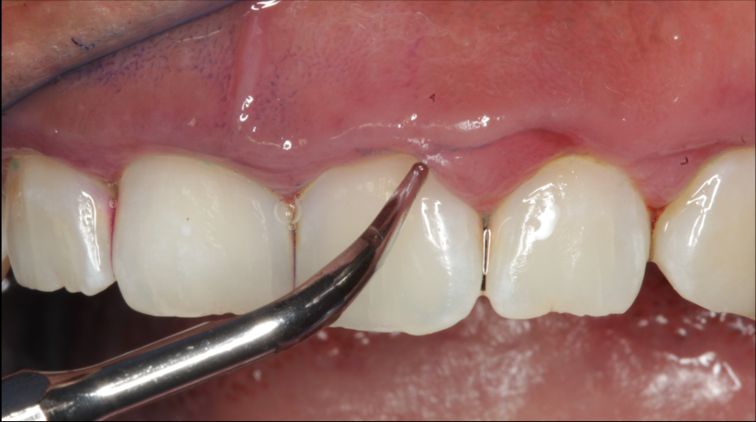

Fotos y videos

La enfermedad periodontal es una patología infecciosa, inflamatoria crónica, de origen bacteriano causada por una comunidad de microorganismos llamada biofilm dental que se adhieren a los dientes, provocando una respuesta inmunitaria que afecta a los tejidos que soportan al diente como el hueso alveolar, ligamento periodontal, cemento radicular. Si esta enfermedad no se controla nos lleva a la primera patología llamada gingivitis con signos clínicos inflamación, sangrado, enrojecimiento en las encías sin perdida ósea. Y si esta no se controla se asevera con presencia de periodontitis con signos clínicos de inflación, dolor, perdida de los tejidos de soportan al diente.